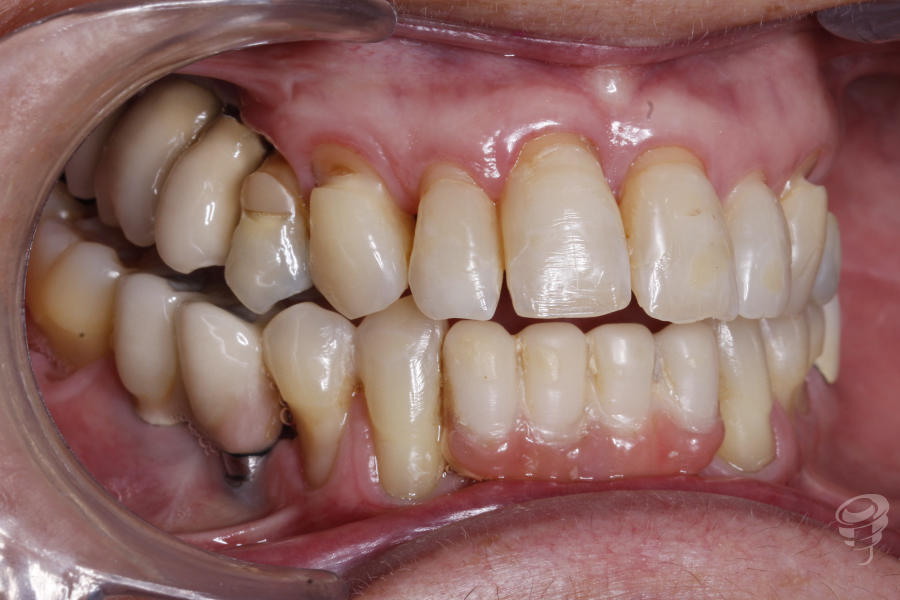

Podemos notar la pérdida de soporte periodontal que hay en el 11 y 21 y una descompensación asimétrica de los márgenes gingivales. Además, mordida abierta anterior y posterior derecha, mordida cruzada posterior bilateral, guías caninas ausentes. Un precario ajuste oclusal y bruxista. Podemos observar notables signos de abfracción en los cuellos 14, 13, 23, 24 y 25.

Figura 1

Figura 2

Figura 3

Figura 4